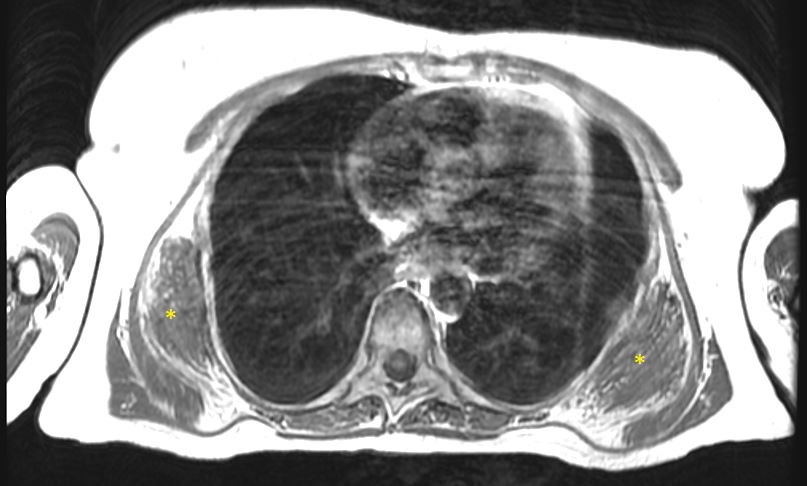

La diagnosi degli elastofibromi sottoscapolari del dorso si basa su una combinazione di esami clinici, imaging e, in casi selezionati, biopsie. Durante l'esame fisico, il medico potrebbe notare la presenza di una massa palpabile nel dorso del paziente, mobile, non dolente, che "scatta" con i movimenti in avanti della scapola. Gli esami di imaging, come la Tomografia Computerizzata (TC) o la Risonanza Magnetica (RM) (Figura 1),

Risonanza Magnetica del torace che mostra due elastofibromi sottoscapolari bilaterali

sono utilizzati per confermare la presenza della massa, valutarne le dimensioni e identificare eventuali coinvolgimenti dei tessuti circostanti. La biopsia può essere necessaria per confermare la natura benigna della lesione, qualora l'imaging ponga il sospetto di una massa neoplastica sarcomatosa.